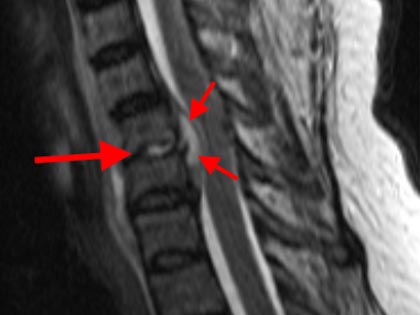

Schmerzsyndrome der Wirbelsäule; Bandscheibenvorfall; Verschleiß der Bandscheiben; Spinalkanalstenose (Verengung des Wirbelkanals); Instabilitäten; Spondylolisthesis (Wirbelgleiten), Myelopathie (Schädigung des Rückenmarkes); Querschnittslähmung; Erkrankungen bei Kinder und Heranwachsenden (z. B. Formveränderungen, Skoliosen, Kyphosen, angeborene Wachstumsstörungen, Verletzungen, Entzündungen, Tumore und Metastasen); Verletzungen des Rückenmarks; Wirbelkörperbrüche; Deformitäten (Formveränderungen, Skoliose, Kyphose); Tumore und Metastasen; Infektionen; Spondylodiszitis (Infektion von Bandscheiben und Wirbelkörper); rheumatische Instabilitäten der Halswirbelsäule sowie zwischen Kopf und Halswirbelsäule; rheumatische Veränderungen der Brust- und Lendenwirbelsäule (z. B. Morbus Bechterew);Verengungen des Foramen magnum; muskulärer Schiefhals; Syndrome durch die erste Rippe; Deformitäten des Thorax (z. B. Trichterbrust, Kielbrust); Erkrankungen und Verletzungen der Rippen; etc.